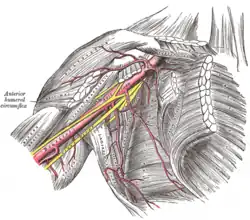

Armpit

The armpit (Latin: axilla) is formed by the space between the muscles of the shoulder.[3] The nerves and blood vessels of the arm travel through the armpit, and it possesses several sets of lymph nodes that are able to be examined.[3] The armpit is formed by the pectoralis major and minor muscles at the front, the latissimus dorsi and teres major muscles at the back, the serratus anterior muscle on its inner surface, and the intertubercular groove of the humerus on the outer side.[3]

Blood vessels

The subclavian artery arises from the brachiocephalic trunk on the right and directly from the aorta from the left. This becomes the axillary artery as it passes beyond the first rib. The axillary artery also supplies blood to the arm, and is one of the major sources of blood to the shoulder region. The other major sources are the transverse cervical artery and the suprascapular artery, both branches of the thyrocervical trunk which itself is a branch of the subclavian artery.[3] The blood vessels form a network (anastamosis) behind the shoulder that helps to supply blood to the arm even when the axillary artery is compromised.[3]